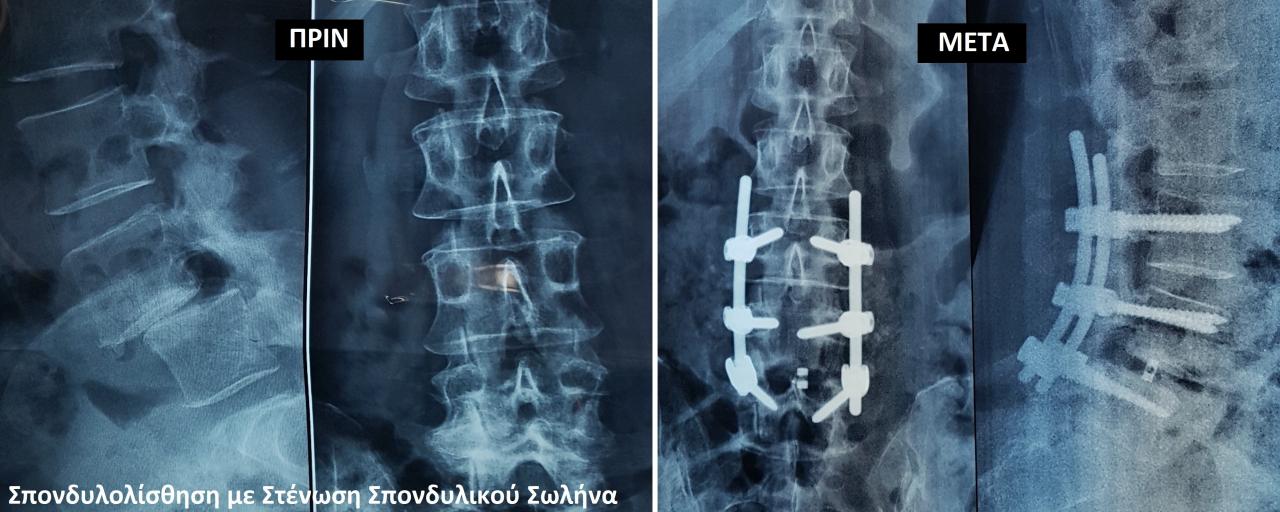

Παθήσεις Σπονδυλικής Στήλης Σκολίωση , Κύφωση Σπονδυλολίσθηση Κυφοπλαστική - Σπονδυλοπλαστική Κήλη μεσοσπονδύλιου δίσκου - Δισκεκτομή Αθλητικές Κακώσεις Αρθροσκόπηση ώμου και γόνατος Ρήξη προσθίου χιαστού συνδέσμου Ρήξη μηνίσκου Ρήξη στροφικού πετάλου του ώμου Ακρωμιοπλαστική Αρθροπλαστική Ισχίου (ALMIS - AMIS) Γόνατος Τραυματιολογία Κατάγματα Άνω - Κάτω άκρου, πυελικού δακτυλίου και Σπονδυλικής Στήλης Παθήσεις άκρας χειρός και άκρου ποδός Εγχύσεις Ενδαρθρικές (γόνατο, ισχίο, αγκώνας, ώμος, καρπός, ποδοκνημική) Σπονδυλικής Στήλης (root block, facet block, Επισκληρίδιες ) Σύνδρομο Καρπιαίου Σωλήνα Trigger Finger Τενοντοελυτρίτιδα De Quervain's Ρίκνωση παλαμιαίας απονεύρωσης ή Νόσος Du Puytren